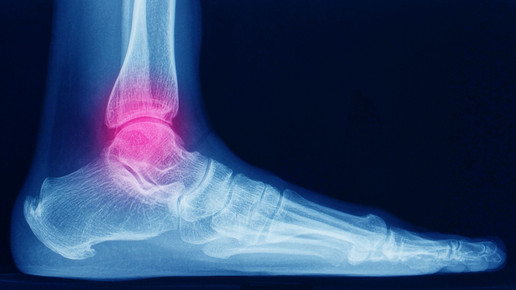

Ein großes Problem der Erkrankung sind Mikroblutungen in Gelenken. Oftmals bemerken die Betroffenen diese Minimalblutungen nicht, und die Gelenke werden auf Dauer geschädigt. Viele Patient:innen besitzen so genannte Zielgelenke – Gelenke, die immer wieder von Mikroblutungen betroffen sind. Hier entwickeln sich am ehesten dauerhafte Schäden. Bei sportlich aktiven Erkrankten ist häufig das Sprunggelenk betroffen. Dauerhafte Einblutungen führen dazu, dass Patient:innen Schmerzen beim Stehen und Gehen entwickeln, die Mobilität wird eingeschränkt.

Rote warme Gelenke – viele Hämophilie-Patient:innen kennen dieses Gefühl. Auslöser hierfür sind Gelenkblutungen. Je nach Blutmenge kann es vorkommen, dass der Körper mit der Entfernung der Erythrozyten überfordert ist und es zu temporären Ablagerungen kommt. Hierdurch kann eine fortlaufende Entzündungskaskade in Gang gesetzt werden. Gelenkspülungen können für Hämophilie-Patient:innen eine Möglichkeit sein, das freigesetzte Blut schnell aus dem Gelenk zu entfernen. Dabei ist der Eingriff der Gelenkspülung selbst klein – Patient:innen müssen kaum mit Risiken rechnen.